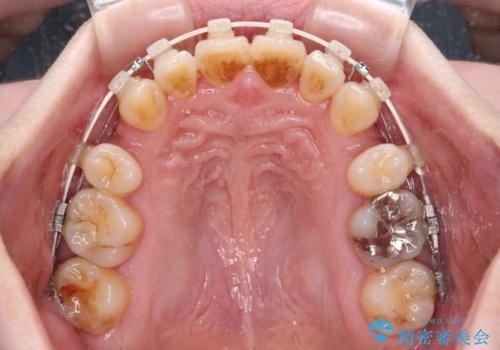

飛び出した上顎前歯と上下のデコボコ 片顎の抜歯によるワイヤー矯正

- 上下前歯のデコボコと、上顎の八重歯を気にして来院された患者様です。

下顎に対して上顎が前方にあり、第一大臼歯による咬合状態は上顎前突であったため、上顎のみ左右の第一小臼歯を抜歯し、ワイヤー装置にて矯正治療を行うこととしました。